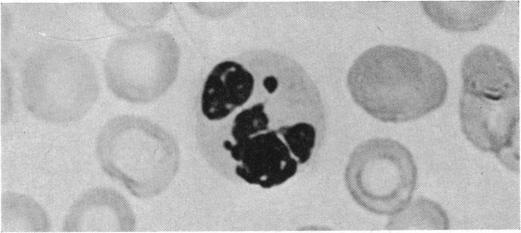

NORTH D P

Br Med J. 1954 Jul 3;2(4878):7-9. doi: 10.1136/bmj.2.4878.7.